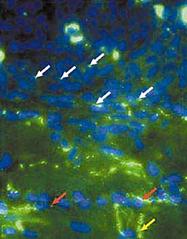

Гистологические исследования показали, что пересаженные в миокард собаки мезенхимальные стволовые клетки человека сформировали между собой и с желудочковыми миоцитами так называемые щелевые контакты - канальные белки, переносящие электрический ток между сопряженными клетками (рис.4) [26]. Полученный пейсмекерный ток проявлял типичные для него свойства: активизировался при гиперполяризации клетки, отвечал на катехоламины и ацетилхолин и блокировался цезием [25].

Рис. 4. Микрофотография гистологического среза миокарда собаки, которой имплантировали человеческие стволовых клеток с экспрессированным геном HCN2 [26]. Белыми стрелками показаны щелевые контакты, образовавшиеся между стволовыми клетками, красными - между стволовыми клетками и кардиомиоцитами, фиолетовой стрелкой отмечено место пролиферации стволовых клеток (интеркалярный, или вставочный диск).